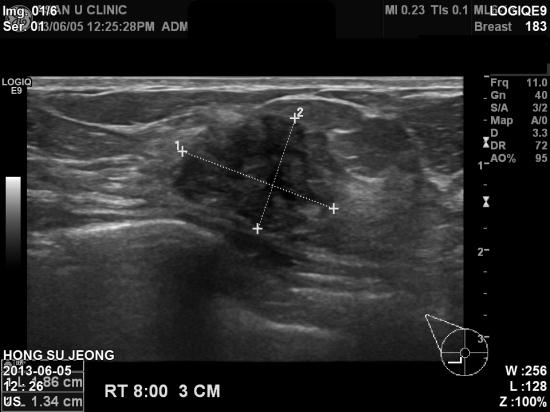

온몸이 아프기 시작하여 여기저기 점검하다가

우측 유방에

멍울을 발견하신 58세 여자분이십니다.

겨드랑이나 다른 부위 임파절 전이 의심소견 없이

우측 유방에만 2.15cm

의 종괴가 침윤성 소엽암으로 진단되셨습니다.